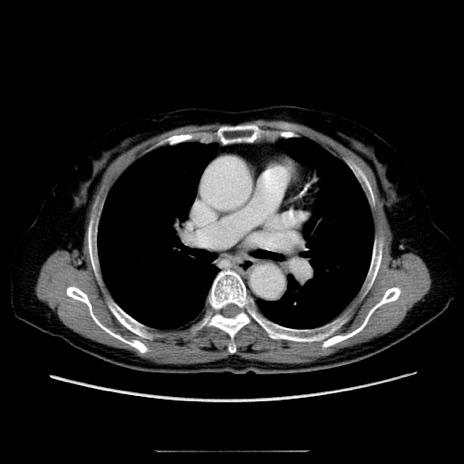

冠状断像

【症例】70歳代女性

【主訴】お腹が張る

【現病歴】1週間くらい前から腹部膨満の自覚あり。昨日夜から増悪したため、本日救急外来受診。

【身体所見】意識清明、BT 36.5℃、BP 165/106mmHg、HR 80bpm、SpO2 98%、腹部:膨満、軟、自発痛・圧痛なし、触診にて不快感あり、腸蠕動音:減弱

【データ】WBC 12600、CRP 1.04